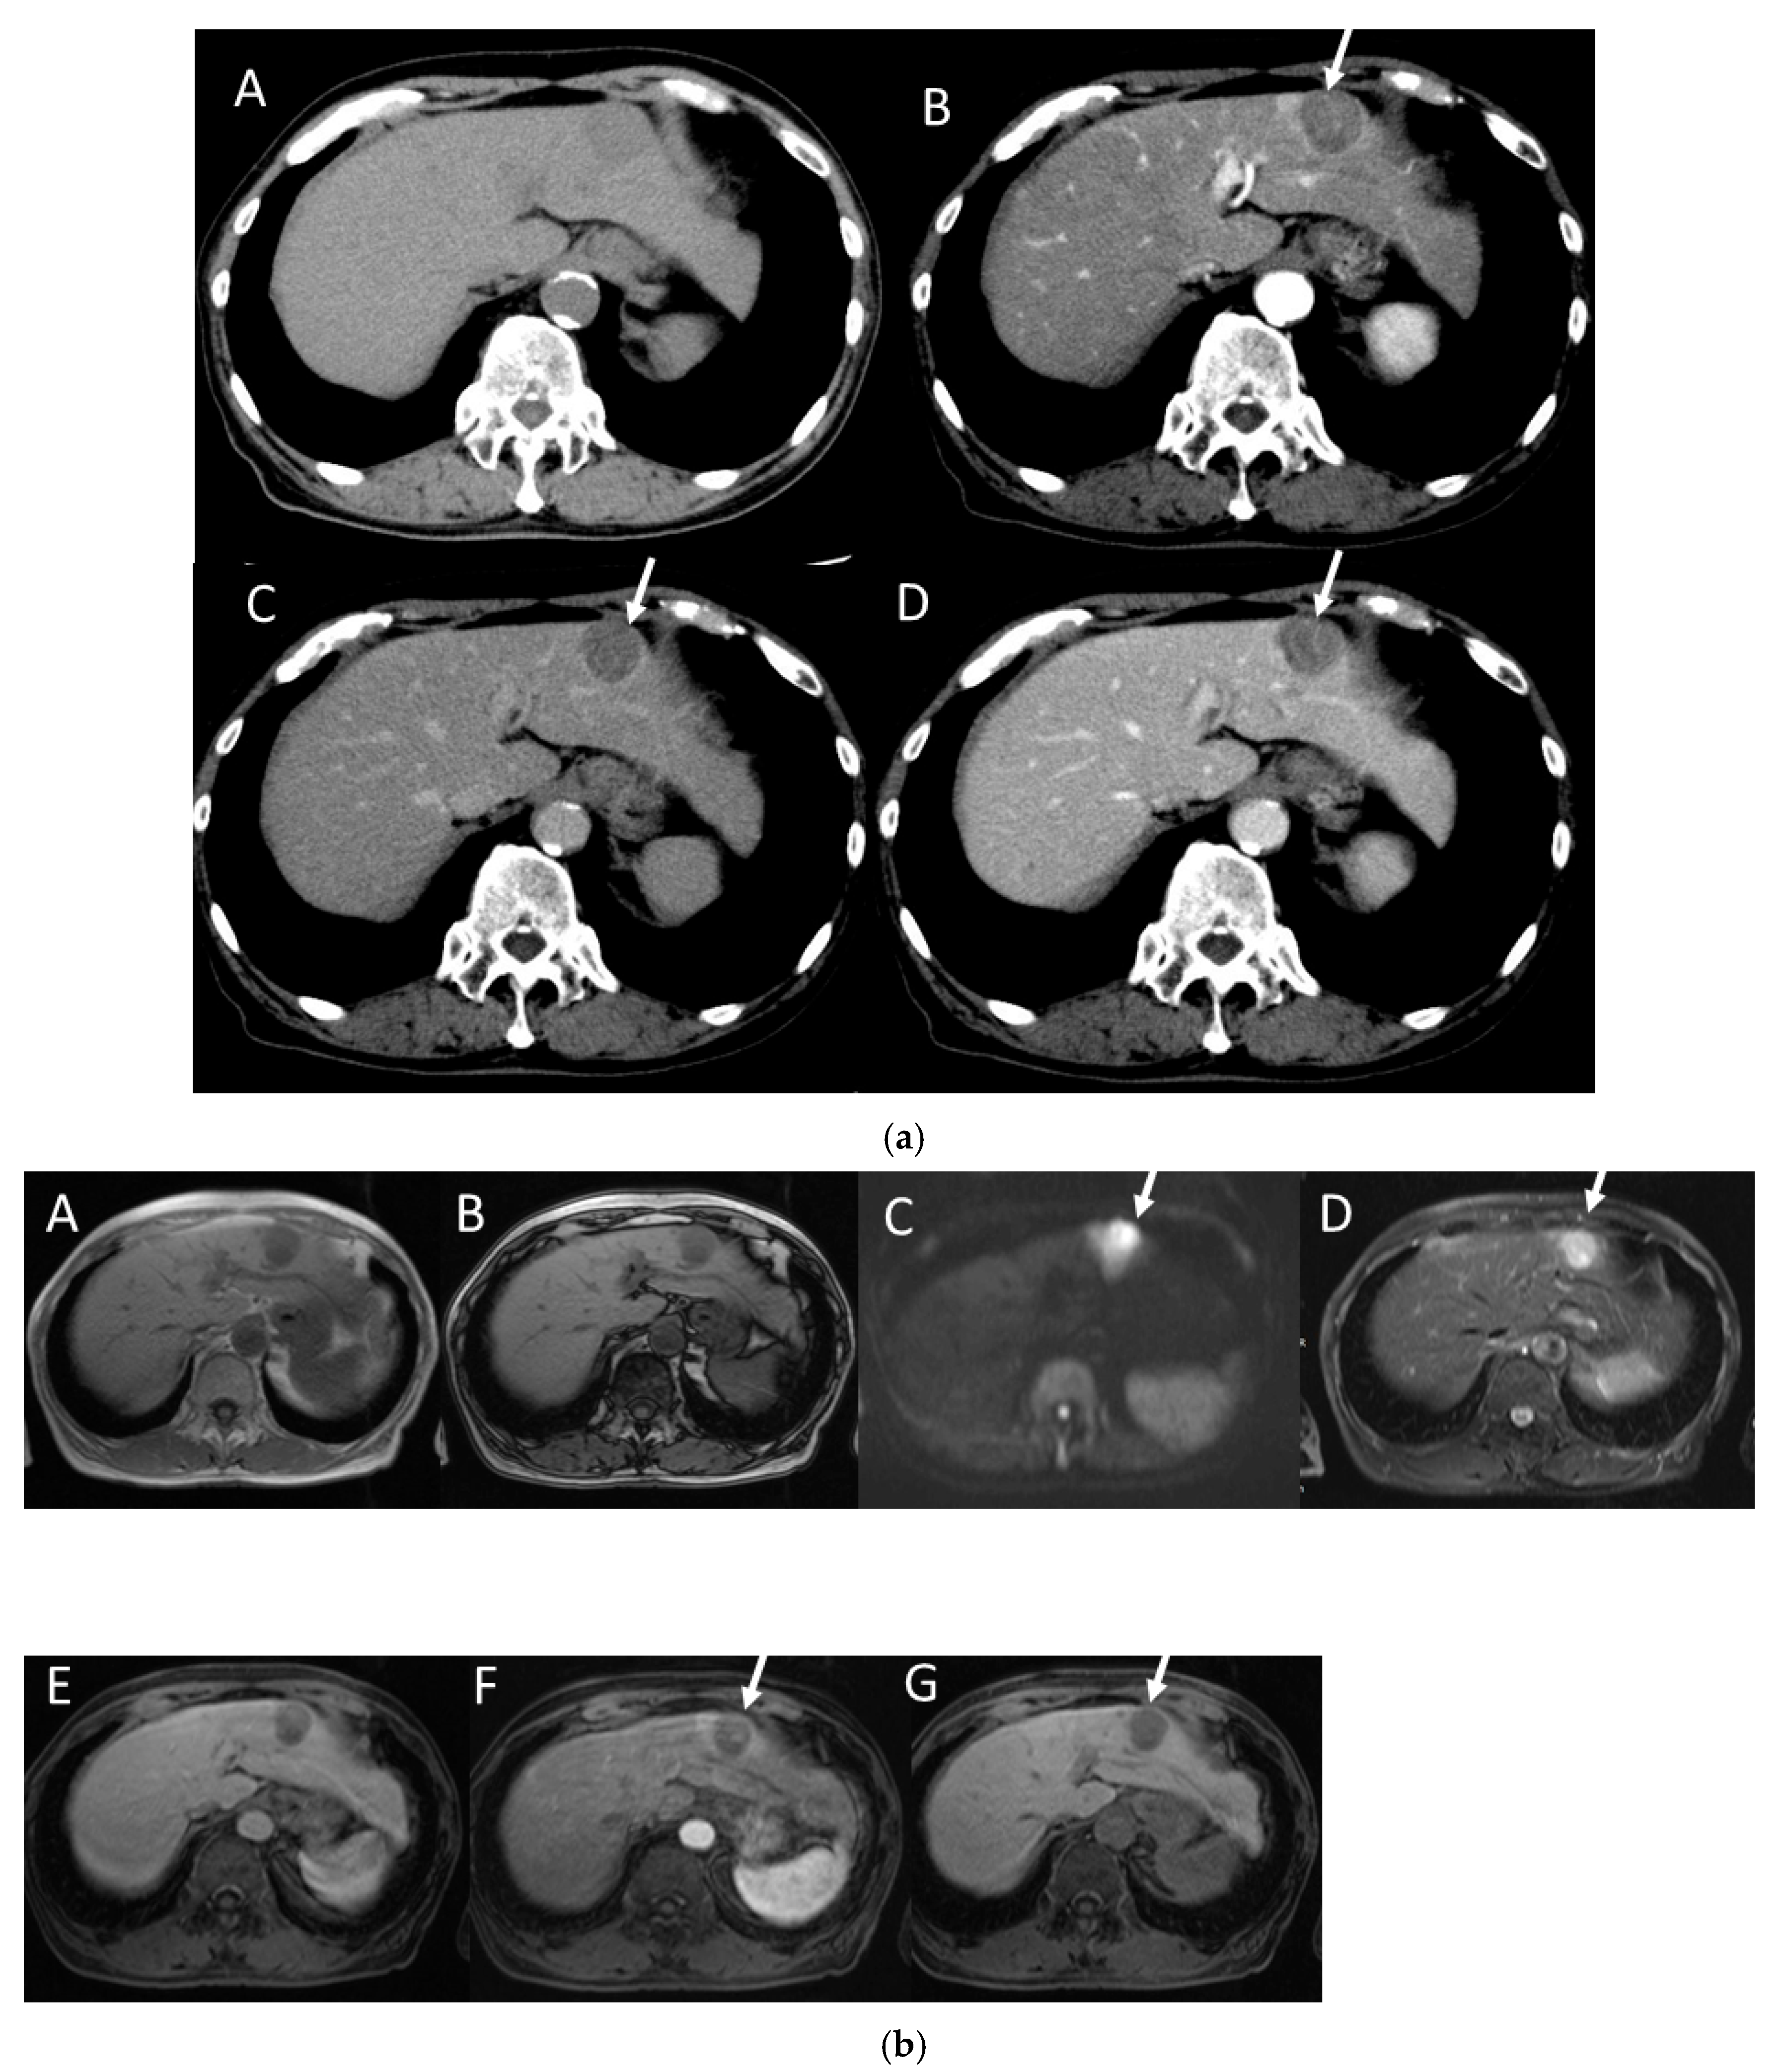

4.7. Combined Hepatocellular and Cholangiocarcinoma (cHCC-CCA)

4.8. Steatohepatitic HCC (SH-HCC)